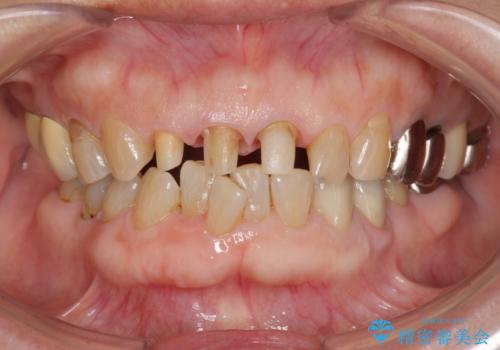

前歯の審美改善

- 70代女性

- 1ヶ月

- 2-5回

- 孫娘の結婚式に合わせて前歯を綺麗にして写真映りをよくしたいと来院されました。

結婚式に合わせて根管治療からのやりかえを短期集中治療で計4回で終える計画を立てます。